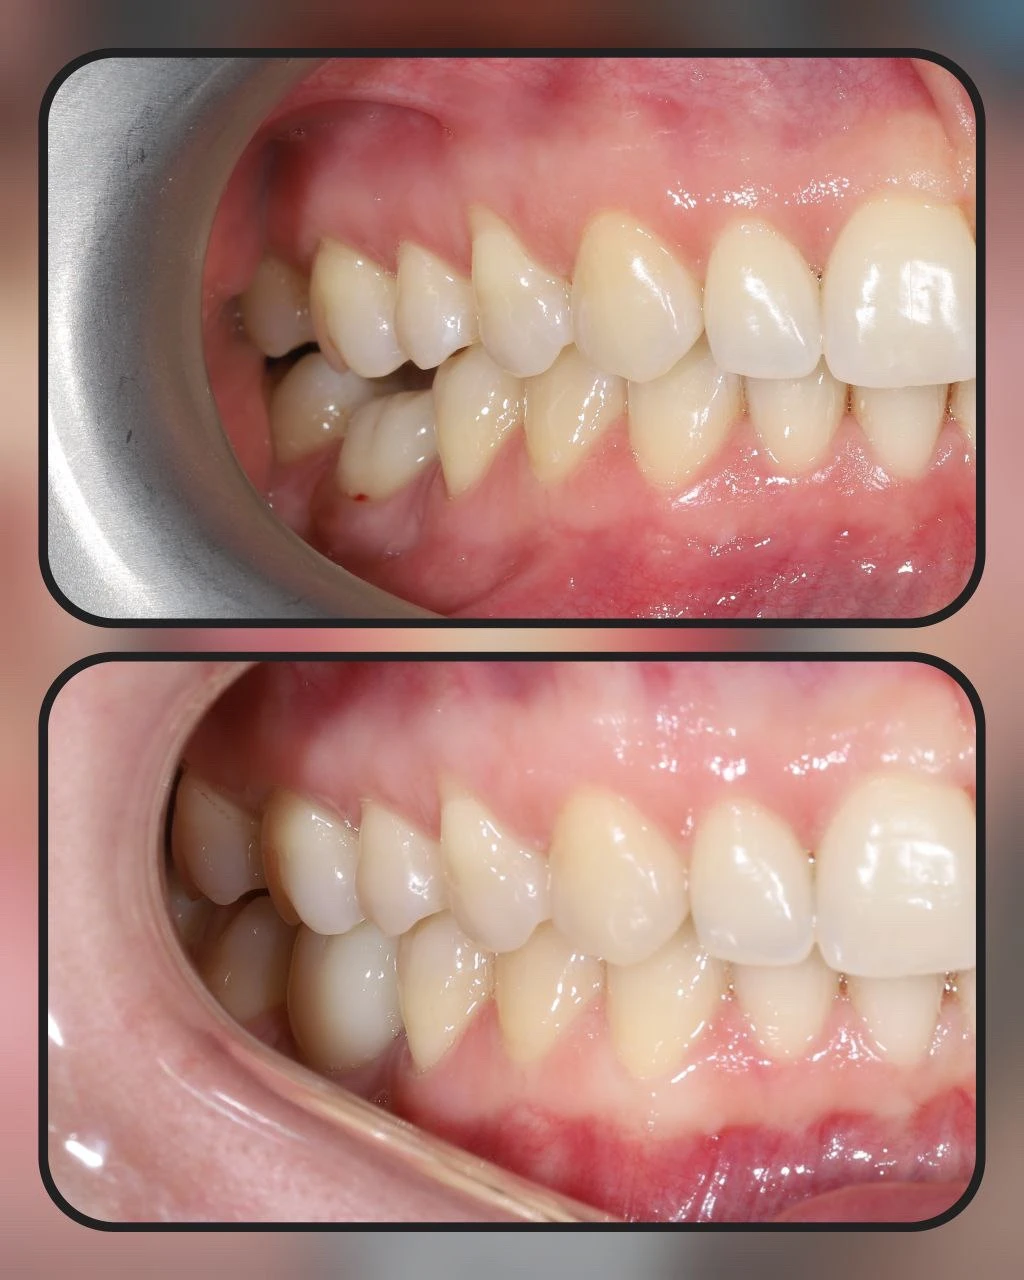

Цирконієва коронка 35 та цирконієва коронка 36 на імпланті